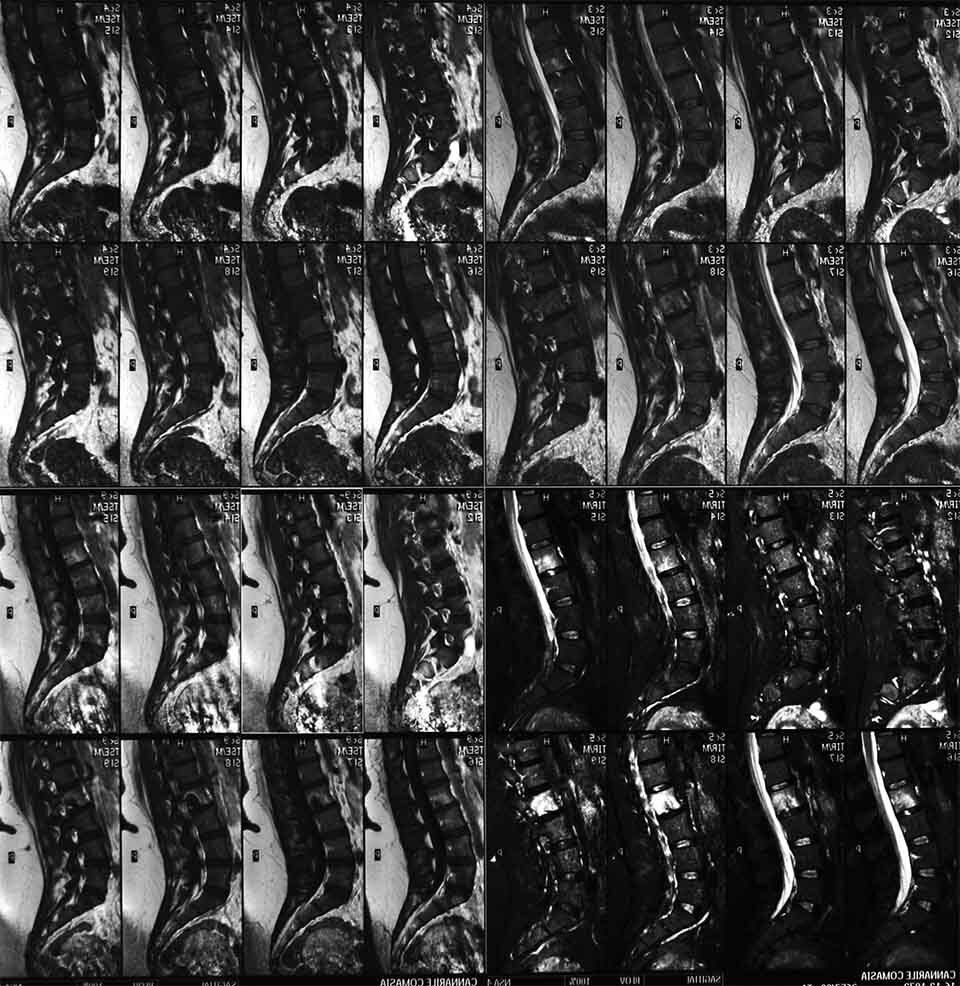

La chirurgia vertebrale rappresenta una delle terapie oncologiche mirate a ridurre o eliminare le masse neoplastiche che provocano il mieloma. La chirurgia vertebrale è una terapia intralesionale che comporta perdite ematiche e necessita di tempi chirurgici molto lunghi. Gli interventi di chirurgia vertebrale, infatti, presuppongono la movimentazione della colonna vertebrale mediante barre, viti e innesti ossei. Richiedi maggiori informazioni riguardo le terapie oncologiche e funzionali destinate alla cura delle fratture vertebrali provocate da mieloma contattando lo studio del dottor Andrea Piazzolla, situato in via Rodolfo Redi 3 a Bari.

Grazie ai nuovi studi e ai progressi della medicina, ad oggi è notevolmente aumentata l’aspettativa di vita dei pazienti che soffrono di fratture vertebrali provocate dal mieloma. Accanto alla chirurgia vertebrale oncologica, infatti, viene sperimentata una terapia funzionale e meno invasiva. La chirurgia vertebrale funzionale, infatti, è in grado di prevenire la perdita delle funzioni neurologiche, ottenendo inoltre una notevole riduzione del dolore e prevenendo l’instabilità vertebrale associata.